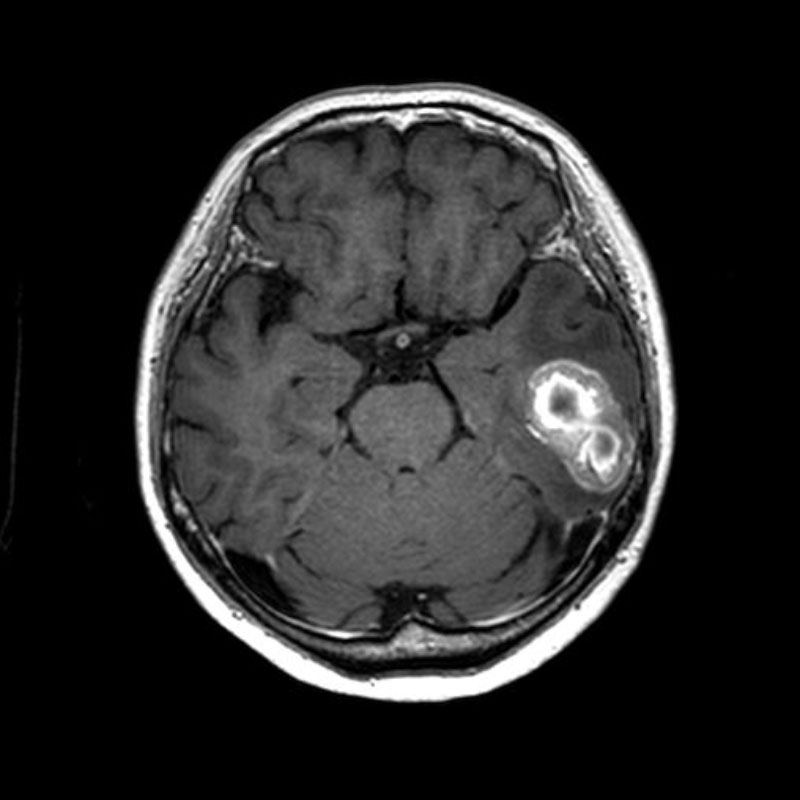

断層撮影

手術前1

手術前2